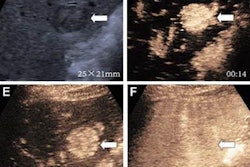

(A) Arterial-phase CEUS image shows a 25-mm segment-8 lesion with non-rim hyperenhancement (arrow). (B) CEUS image in portal-venous phase shows corresponding early washout (arrow). (C) CEUS image in late phase shows corresponding late and mild washout (arrow). (D) CEUS image in Kupffer phase shows marked Kupffer defect (arrow). The patient, a 71-year-old woman, also underwent evaluation by dynamic contrast-enhanced MRI using gadoxetate disodium. (E) Axial arterial-phase image shows 23-mm segment-8 lesion with non-rim arterial phase hyperenhancement (arrow). (F) Axial portal-venous phase image shows corresponding non-peripheral washout (arrow). This observation was classified as LR-M by modified CEUS criteria using perfluorobutane, and as LR-5 by CT/MRI LI-RADS v2018. The pathologic diagnosis based on surgical resection was intrahepatic cholangiocarcinoma. Images courtesy of ARRS.The LR-5 category on CEUS shows "very high" specificity but has lower sensitivity than CT/MRI. But perfluorobutane microbubbles for CEUS have a particular phase called Kupffer that enhances liver parenchyma -- an effect not seen when CEUS is performed using conventional contrast agents, the group noted. They suggested that these Kupffer-phase findings could improve sensitivity in the LR-5 category.